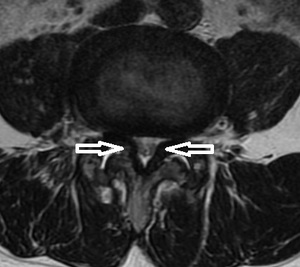

腰部MRI 側面像 腰部MRI 水平断像

自宅で立ち上がろうとした時にぎっくり腰になり、当接骨院へ来院されました。男性からここ1年、腰、股関節から膝に

痛みと痺れが取れないと訴えがありました。精査依頼先の病院にてMRI検査を実施。腰部脊柱管狭窄症と診断

されました。(左右上画像の矢印)

腰部脊柱管狭窄症とは、先天性や発育性によるものは少なく、腰部への負担や加齢による変形性変化によって

(椎間板の突出や椎体の骨棘、黄色靭帯の肥厚など)脊柱管に狭窄をきたし、脊髄(神経)が圧迫される疾患です。

感じ方や症状によって個人差がありますが、代表的な症状は、

①間欠性跛行: 起立や歩行を続けると臀部、もも(大腿)、下腿などに痺れや痛みが生じ、前かがみで2~3分休みと

また歩行が出来るようになります。

②Sensory March: 歩行と共に一定方向に痺れが広がっていきます。

③排尿異常: 尿失禁、排尿困難などや会陰部の痺れ感、性機能不全などがあります。